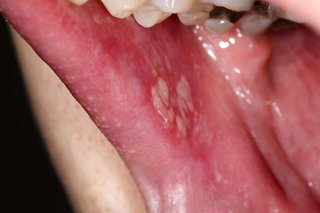

White patches of lichen planus in the mouth of someone with white skin.

White patches in your mouth may be a symptom of lichen planus.